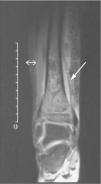

Ante la sospecha de osteomielitis, se inició tratamiento antibiótico empírico intravenoso con cloxacilina y cefotaxima. Por la persistencia de la fiebre y del dolor intenso, tras 48h de tratamiento antibiótico se realizó resonancia magnética en la que se apreció una imagen compatible con una fractura tibial distal por epifisiólisis y signos de infección ósea con absceso subperióstico. Se realizaron desbridamiento y curetaje, y en el cultivo de material óseo se aisló S. aureus con resistencia a oxacilina y sensible al resto de antibióticos no betalactámicos. Con estos resultados se instauró antibioterapia con clindamicina intravenosa con buena respuesta clínica. Asimismo, se confirmó la colonización nasal por SARM en el paciente y sus familiares, y se procedió a la administración de mupirocina intranasal. El seguimiento posterior permitió documentar la erradicación del estado de portador y de las infecciones cutáneas recurrentes en todos los casos.

Nuestro paciente presentó una osteomielitis estafilocócica complicada con un absceso subperióstico (fig. 1). El patrón fenotípico de resistencias fue el característico del SARM-AC y no hubo contacto personal ni familiar con el medio hospitalario. El caso es significativo, además, porque existió una transmisión intrafamiliar de S. aureus con una elevada expresividad clínica, posiblemente en relación con una virulencia incrementada del germen, aunque este aspecto, al igual que las resistencias genotípicas características de los SARM-AC (SCCmec tipo IV), no pudieron ser documentados desde el punto de vista molecular.